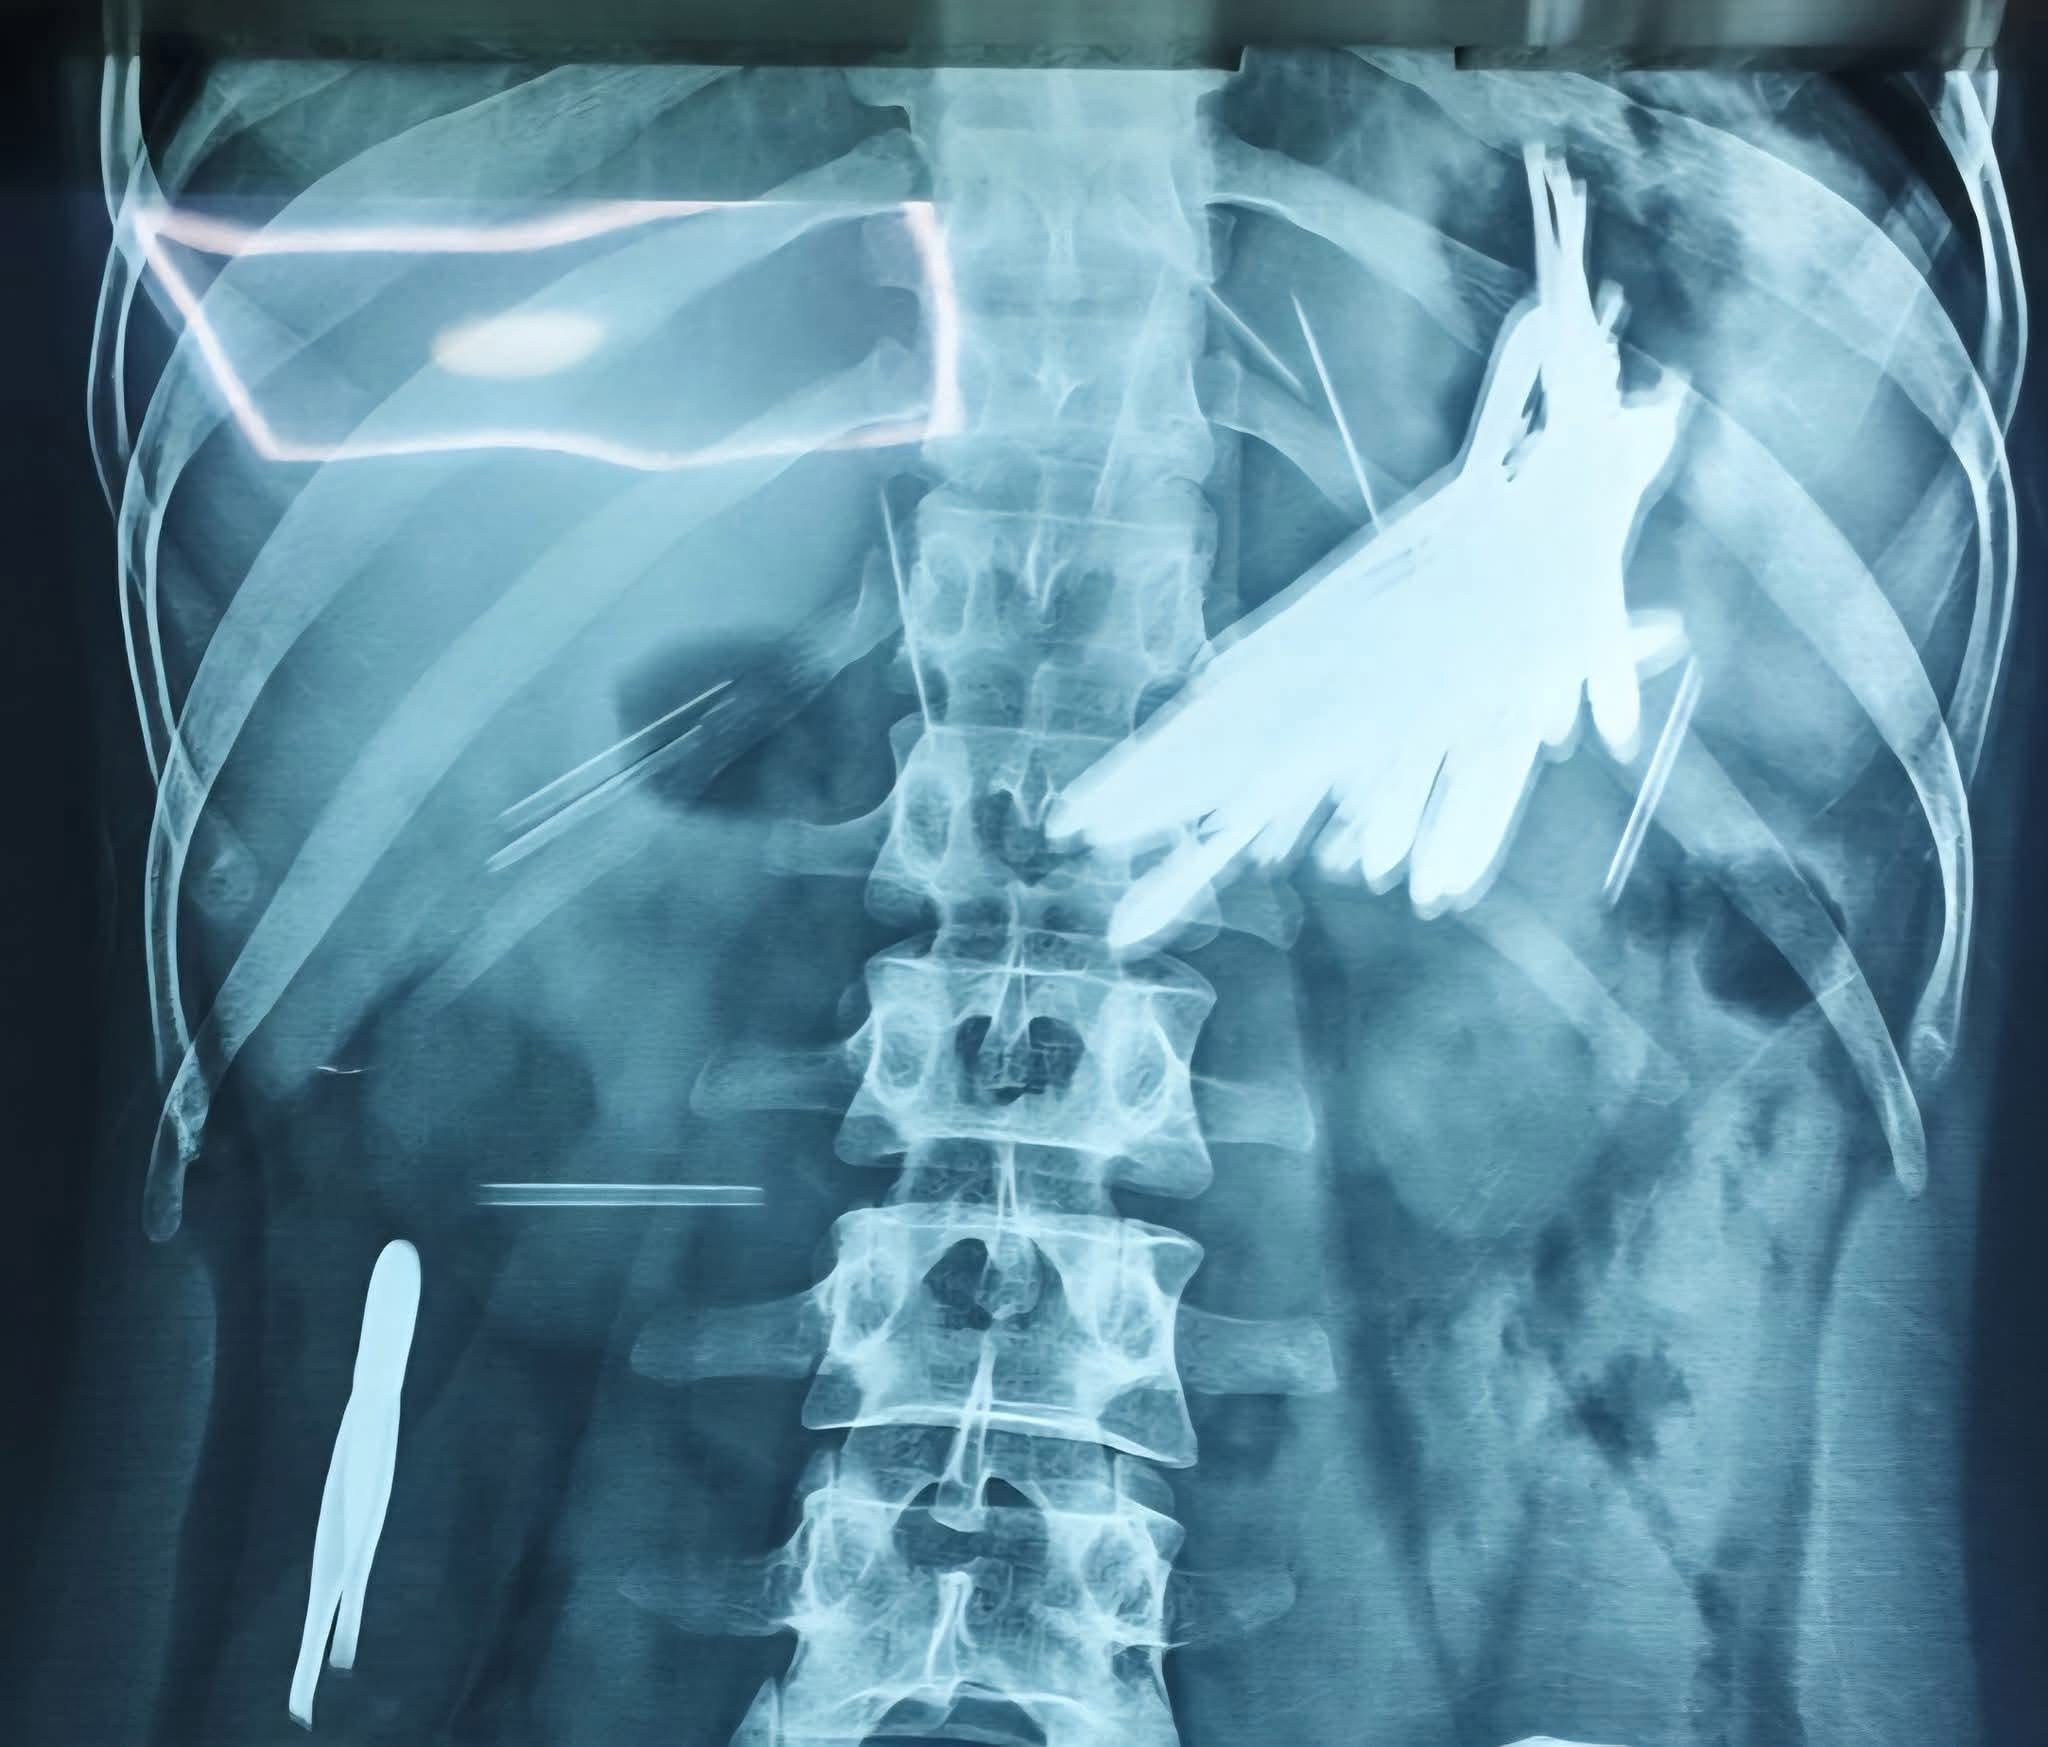

وقالت صحة السليمانية في بيان إن “فريقا طبيا في ردهة التنظير البطني والتخدير بمستشفى أمراض الجهاز الهضمي والكبد التعليمي، نجح في استخراج 24 قطعة معدنية من معدة شاب عشريني”، مبينة أن “القطع تتألف من 16 ملقط شعر و8 إبر وغلافي ملقط”.